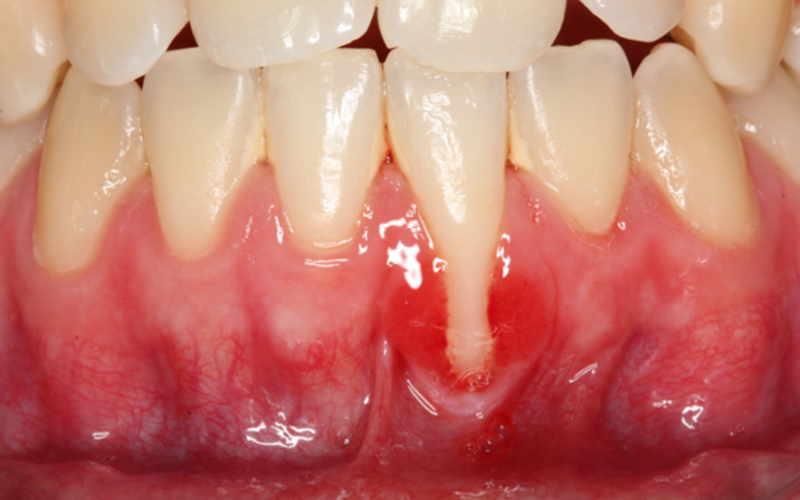

Gingival retraktion defineres som en apikal forskydning af den gingivale margin i forhold til emaljecementgrænsen (ECG), hvilket resulterer i fæstetab og eksponering af rodoverfladen til det orale miljø.

Gingivale retraktioner er meget almindelige i populationer med høj standard af mundhygiejne, hvor de ofte er relateret til traumatisk tandbørstning – særligt på de bukkale flader, hvor der også hyppigt ses usurdannelse cervikalt. Forekomsten blandt personer over 64 år er 88 %, og 50 % af de 18-63-årige rammes af gingival retraktion på minimum ét sted. Langt de fleste tilfælde kræver ikke behandling.

Der er flere prædisponerende faktorer, som anses for at spille en rolle i udviklingen. En af de hyppigste årsager, der er associeret med gingivale retraktioner, er traumatisk tandbørstning. En anden faktor er manglende knogle omkring tænderne i form af dehisenser og fenestrationer og ydermere tandens position i tandbuen. Ofte er årsagen en kombination af flere faktorer.

En tynd parodontal fænotype (se Tabel 1) har en tendens til at udvikle flere gingivale retraktioner end en tyk fænotype – det er fastslået i litteraturen.